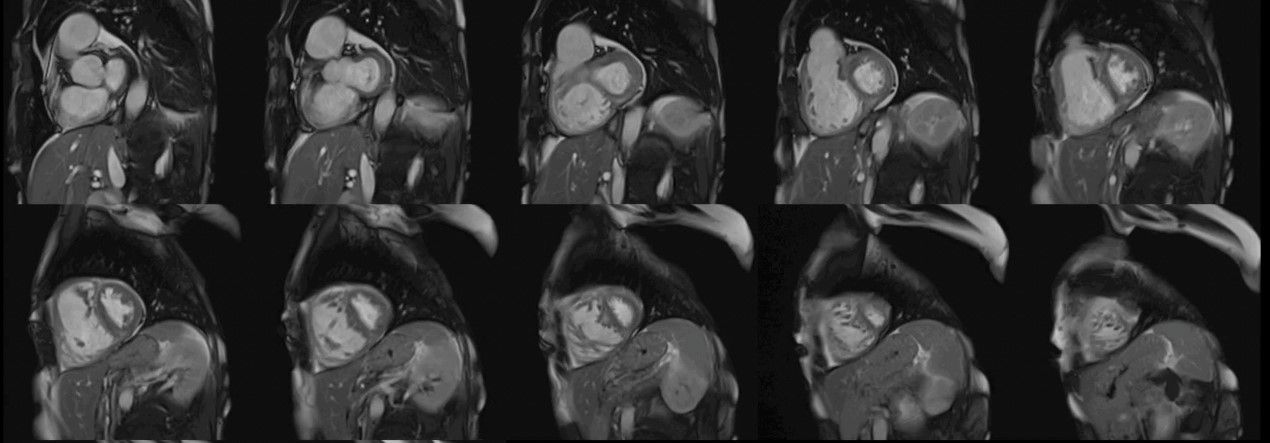

The CMR pulse sequence used for assessment of cardiac function is the balanced steady-state free precession (bSSFP). It represents the gold standard for the evaluation of cardiac anatomy, mass, wall motion, and right/left atrial/ventricular dimensions and function [11]. This is of particular value in patients with autoimmune disease, where RV pathology can play an important role in the generation of VAs and may not be adequately imaged using echocardiography [11] (Fig. 1).

Fig. 1.

Fig. 1.Biventricular function assessment. Short axis SSFP for function assessment in a patient with systemic sclerosis and pulmonary hypertension. Dilation of the right ventricle with flattening of the interventricular septum due to pulmonary hypertension can be observed. SSFP, steady-state free precession.